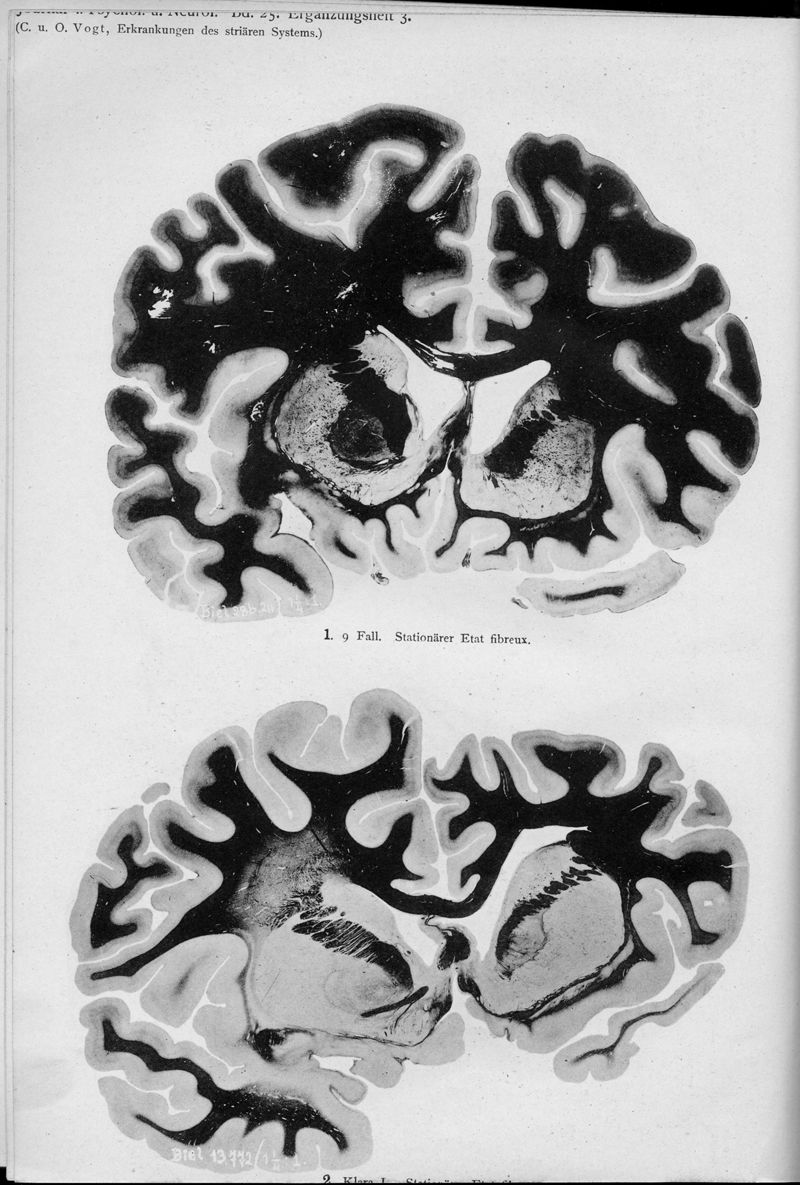

VOGT, Cécile / VOGT, O.

In : Journal für Psychologie und Neurologie,

1920, Vol. 25, pp. 627-846